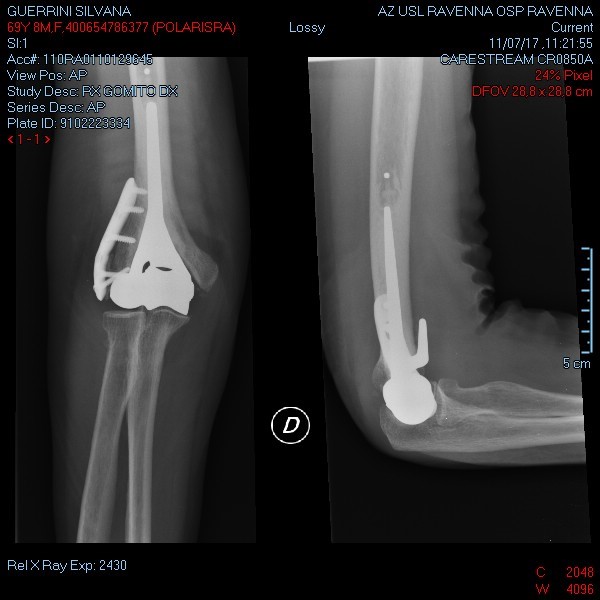

1) Protesi totale di gomito: riproduce la superficie articolare del gomito mediante due componenti, una omerale e l’altra ulnare (Fig. 3). L’accoppiamento tra le componenti protesiche che scorrono tra loro durante il movimento del gomito è metallo-polietilene. A seconda della presenza o meno di una cerniera -che crea un vincolo meccanico tra la componente omerale ed ulnare- le protesi totali di gomito si dividono in:

- con cerniera (linked): modelli che presentano una stabilità intrinseca e consentono un più ampio spettro di indicazioni (Fig. 3). Attualmente tali modelli sono i più comunemente utilizzati in Italia e Stati Uniti.

2) Emiartroprotesi omerale: prevede la sostituzione della sola estremità distale dell’omero con una protesi in metallo che ne riproduce la forma (Fig. 4) e che si deve bene adattare alla superficie ulnare e radiale contrapposta.

Questo impianto di più recente introduzione trova indicazione tipicamente in fratture dell’omero distale pluriframmentarie con impossibilità alla sintesi, in pazienti anziani con discrete richieste funzionali, in cui una protesi totale richiederebbe delle restrizioni maggiori da parte del paziente.